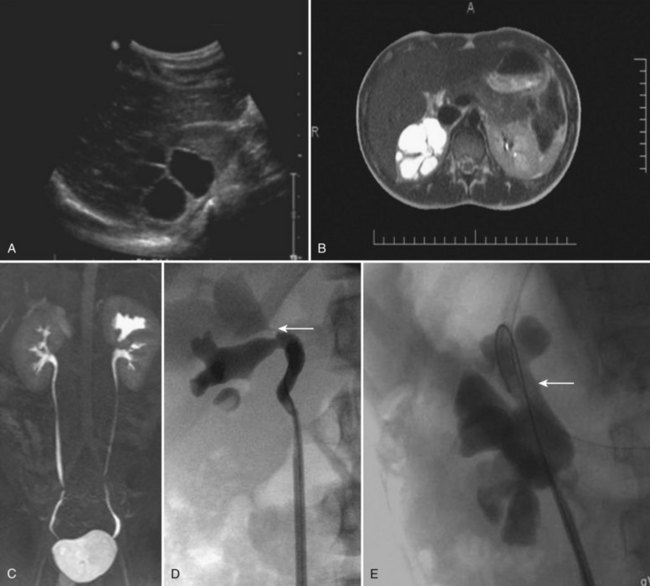

Figure 117–23 Infundibular stenosis of right upper pole calyx. A, Sagittal ultrasonogram. B, Axial T2 images. C, Coronal MR urogram. D, Right retrograde pyelogram shows no filling of the stenotic infundibulum (arrow). E, Right retrograde pyelogram following laser incision and balloon dilation of the infundibulum (arrow).

(Courtesy of Dr. Pasquale Casale.)

Infundibulopelvic stenosis is usually bilateral and is commonly associated with vesicoureteral reflux, suggesting an abnormality of the entire UB (Kelalis and Malek, 1981). Patients usually present with urinary infection, hypertension, or flank pain. Sometimes, an asymptomatic child with multiple anomalies is found to have this condition. Despite extensively dysmorphic kidney features, the function is either normal or only slightly affected (Kelalis and Malek, 1981). In Husmann’s study of 21 patients with the longest follow-up to date (median of 11 years), 90% had bilateral renal disease (Husmann et al, 1994). Ten patients had bilateral infundibulopelvic stenosis, 6 had a contralateral dysplastic renal unit, and 3 had contralateral URA. Renal insufficiency or end-stage renal disease developed in 8 (37%), all of whom had bilateral kidney anomalies. Renal biopsies in those with end-stage renal disease demonstrated renal dysplasia proximal to the stenotic infundibuli and varying degrees of glomerulosclerosis of the glomeruli that were not involved in the regions with dysplasia. They proposed that the decreased total functional renal tissue leads to hyperfiltration injury. They suggested that routine infundibulotomy should not be performed, but endoscopic or percutaneous surgery should be considered for increasing hydronephrosis (see Fig. 117–23). More recently, Nurzia and colleagues (2002) recommend monitoring of renal function to include a baseline and yearly serum creatinine level, estimation of glomerular filtration rate, and urinalysis. Prevention of hyperfiltration injury with calcium channel blocking agents, angiotensin-converting enzyme inhibitors, and dietary restriction of protein should be considered when a decline in renal function with azotemia, proteinuria, or hypertension occurs (Paddu et al, 2009).